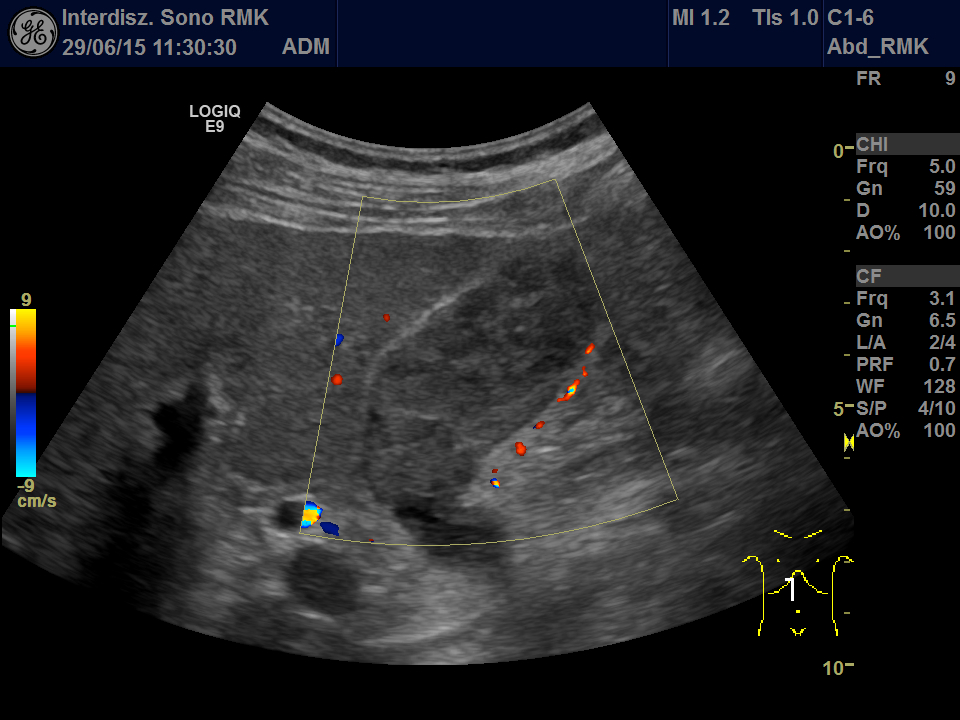

A 61 year old man was admitted to our hospital due to acute GI-bleeding. The man had been completely healthy until than and did not need any medications. One year ago a small melanoma on the head had been removed in toto. Routine ultrasonography before endoscopy showed echogenic material in the gallbladder (Fig. 1 + 2, Video 1). First gallbladder sludge was suspected. Because of its inhomogeneity in an additional linear array examination and a Doppler examination performed. Here arterial vessels in the gallbladder lumen were detected, thereby proving solid tissue (Video 2).

Video 2: Second look using the linear array and Doppler: Using low PRF several arterial branches inside the gallbladder can be detected. Note the inhomogeneity of the echos in the lumen.